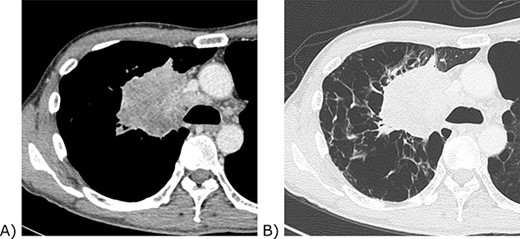

The patient was a male in his 40s. He visited an orthopaedic practitioner for multiple joint pain. No arthritis or rash was observed, but a tumour was detected on his chest X-ray, so he was referred to us (Fig. 1). He was a current smoker with a smoking index of 600. He did not have a past medical history other than chronic obstructive pulmonary disease. His mother suffered from lung cancer. He had an allergy to dairy products. A 9-cm irregular-shaped tumour was revealed in the hilum of the right lung by computed tomography (Fig. 2). The tumour seemed to invade the superior vena cava and azygos vein. Transbronchial biopsy was unsuccessful. The tumour was believed to be a non-small-cell lung cancer of clinical stage IIIB. As the tumour grew quickly, prompt surgery was scheduled.

Chest computed tomography of the tumour. (A) Contrast-enhanced mediastinal window view. The tumour invaded the confluence of the superior vena cava and azygos vein. (B) Lung window view. The background lung was emphysematous.